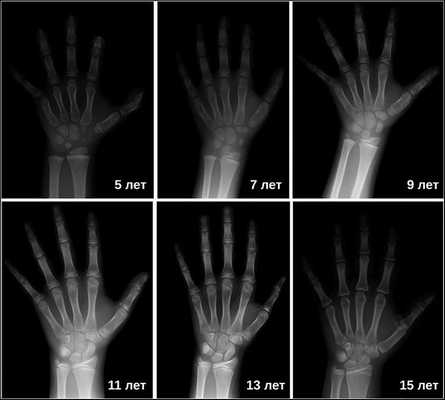

Затем врачи определяют костный возраст. Сделать это можно с помощью рентгена или УЗИ запястья. В норме костный возраст может отставать или опережать паспортный на два года.